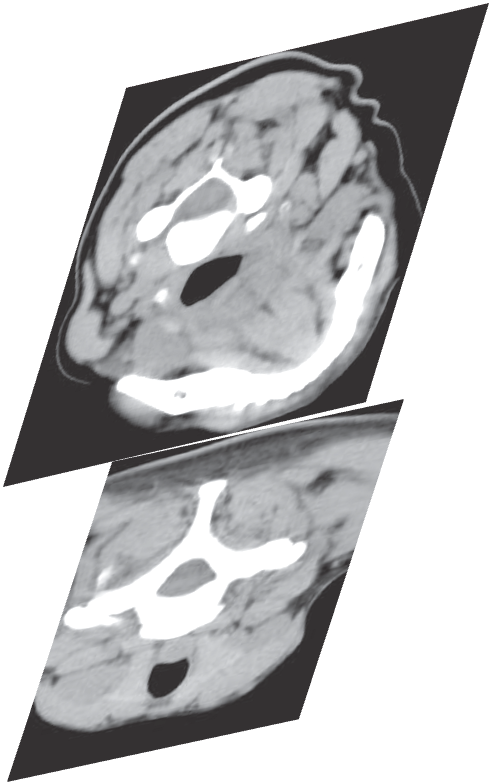

Professor Con Yiannikas

MUSCLE SELECTION